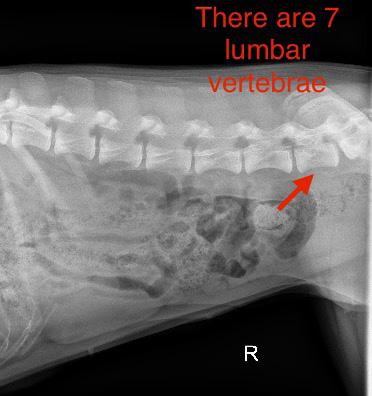

In a veterinary clinic, while conducting a clinical examination of a dog, one might observe additional signs such as heightened respiratory

sounds, muscle wasting, and particular attention should be given to assessing cranial nerve reflexes. The diagnosis is most easily made using radiographic imaging, sometimes concurrently with contrast imaging, which, by staining the pathways, reveals expansions. In brachycephalic breeds, smaller, more tortuous placements of the esophagus are normal and should not be confused with megaesophagus.

DIAGNOSIS OF MEGAPHAGUS

One day our 12-year-old Rhodesian Ridgeback female began to cough, with food coughing up again and again. Since there was no improvement in sight, we consulted our veterinarian. After my description of the problem and a subsequent X-ray with contrast medium, the diagnosis was made quickly. Hanna has pneumonia caused by a Megaphagus.